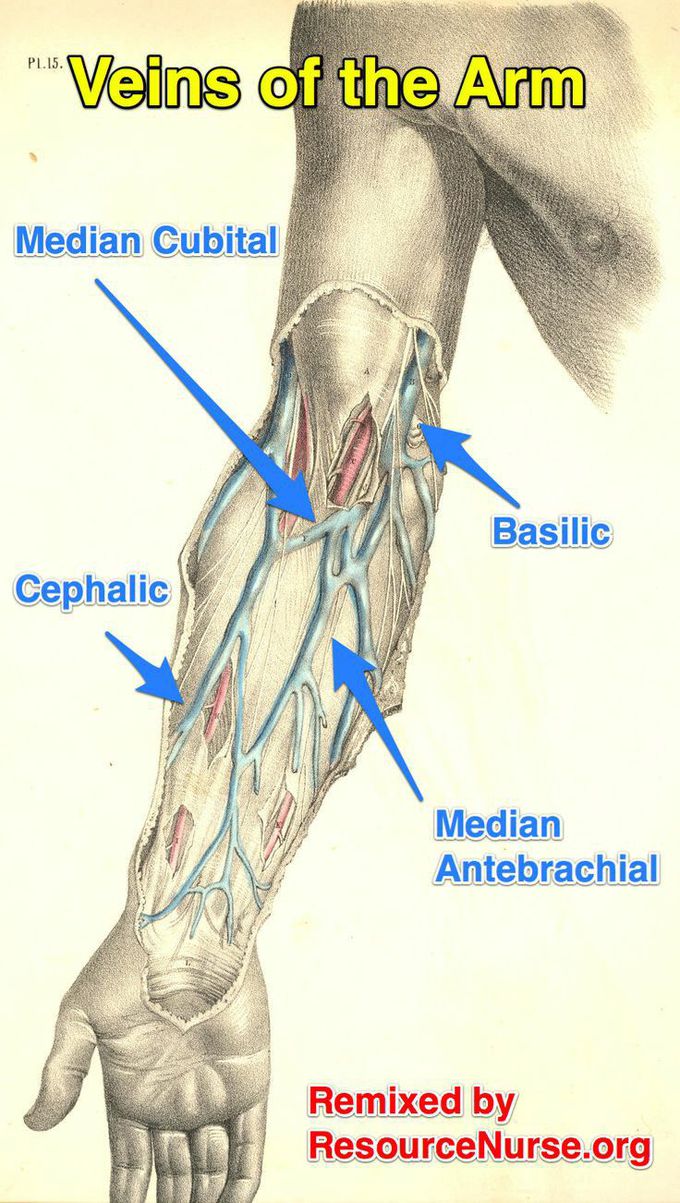

VEINS OF THE ARM - MEDizzy

medizzy.com

medizzy.com

Anatomy, shoulder and upper limb, veins. Image of the superficial veins of arm and forearm. Vein cephalic veins arm access forearm superficial accessory cardiovascular triceps modernheal important whatsapp twitter anatomicvariants anatomyatlases